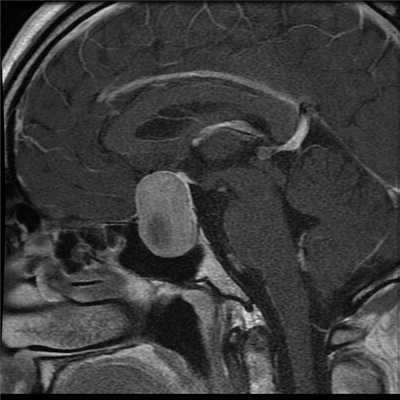

МРТ гипофиза. На МР-томограмме определяется гигантское образование неоднородной структуры (обведено) — макроаденома гипофиза.

Чаще всего исследование проводится для диагностирования аденомы гипофиза и определения ее величины: микроаденомы (до 10 мм), макроаденомы (10—30 мм) и гигантской аденомы (более 30 мм). Также с его помощью обнаруживаются неоднородности структуры, асимметрия границ, изменения положения воронки гипофиза и ее структуры, а также деформации окружающих костных тканей.

Наиболее часто на томограммах обнаруживают аденому гипофиза - доброкачественное новообразование, исходящее из передней доли. Опухоли могут произрастать из любого отдела питуитарной железы, что вызывает многообразие клинических проявлений. Аденома гипофиза локализуется в области турецкого седла, при значительном росте возможно распространение на костные пазухи, желудочки головного мозга, базальную поверхность больших полушарий. Вышеописанные структуры врач может рассматривать в виде многоплоскостных объемных изображений, состоящих из множества срезов, что позволяет уточнить:

- размеры и границы опухоли;

- ее взаимосвязь с окружающими структурами - супраселлярной и мозговой цистернами, перекрестом зрительных нервов, пазухой основной кости, спинкой и бугорком седла, кавернозными синусами и пр.;

- предположительный характер (доброкачественный или злокачественный, первичный или метастатический, окончательная верификация доступна после морфологического исследования). Анализируют постконтрастные снимки, интенсивность накопления красителя (аденомы в подавляющем большинстве задерживают препарат медленнее, чем ткани гипофиза, для злокачественных опухолей характерен усиленный ангиогенез). Дифференциацию проводят с краниофарингиомой, кистой кармана Ратке и арахноидальной жидкостной полостью, имеющих схожие признаки на МР-сканах.

Специалист делает вывод о наличии новообразования гипофиза при обнаружении деформации дна одноименной ямки, асимметрии самой железы, неоднородности ее структуры, смещении воронки от срединной линии.